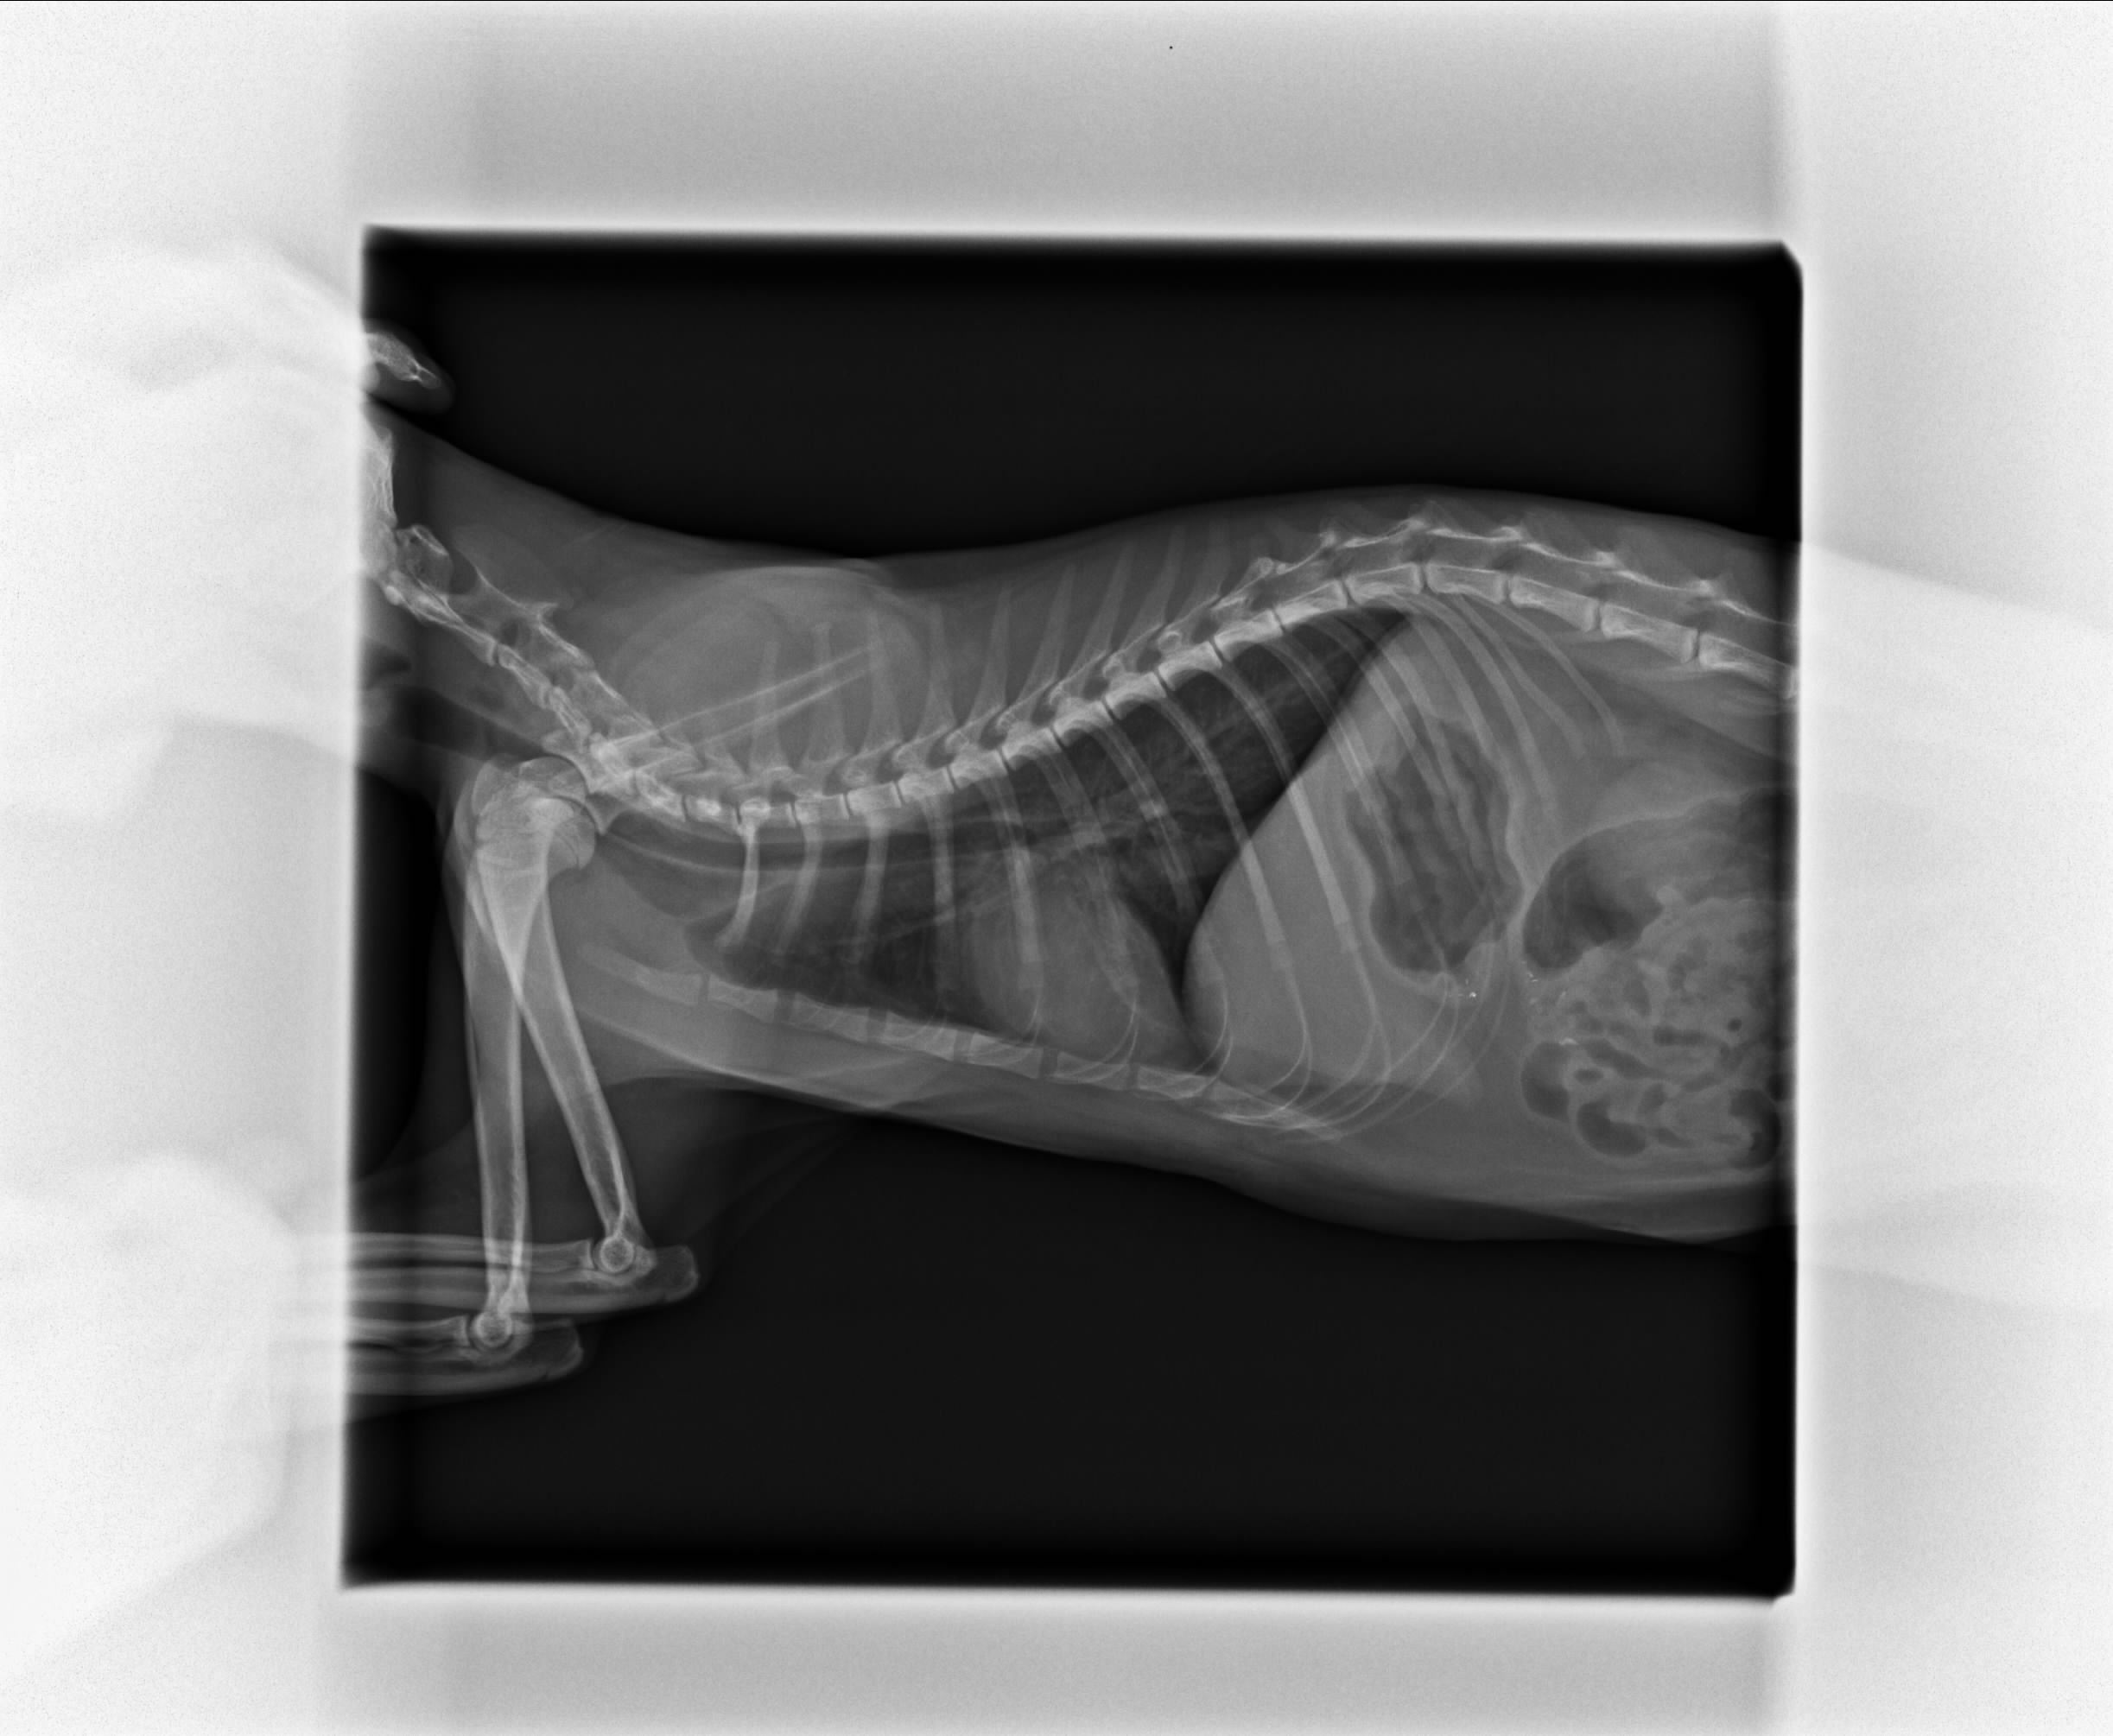

主題: 在垃圾堆等死的貓 申請者姓名: Amanda Chen 花色: 申請日期: 2014-04-14 17:36:28 申請者部落格: 申請者臉書網址: https://www.facebook.com/?ref=home#!/amanda.chen.714 所在縣市/合作醫院: 高雄市/恩澤動物醫院 治療費用: 12230元 需求人數: 15人 已結案 (2014-06-20 16:27:30) 報名人員: Amber Chung(已付款)、Candace Shiue(已付款)、SW(已付款)、catholic(已付款)、Jolin Lin(已付款)、謝小馬(已付款)、吳小海(已付款)、naifulei x8(已付款)、 候補人員: 動物病情說明: Q將(小男生)在半夜被車撞到.躲在垃圾堆旁一動也不動.我在3/30上班時去後巷尋了一下.看見Q將.疑為他生病了.抱起他一直哭哭.才發現他的嘴巴附近佈滿鮮血.先帶回公司廁所安置.臨時找不到運輸籠.趕緊把它裝在洗衣籃內送醫.星期日只有杜專科有開.馬上前往.醫生先檢查外觀.傷口.除蚤.照了X光.X光初步判斷.沒有氣胸.沒有橫隔膜破裂.膀胱因尿都排光了.看不出有無破裂.腹腔的臟器還算正常.四支也沒看到骨折現象.撞擊點在鼻腔頭部.先輸液進行治療.觀察三天是否有腦症盪或其他慢性內出血.也幫牠做了血檢.Q將有嗜睡高溫狀態.血壓有點白血球偏低.預估住院至少5日. 動物近況說明: Q將一直沒有食慾.醫生建議延長住院一週治療.並增加鼻胃導管灌食.怕Q將一直沒有進食會營養不足.沒天至院關心Q將現狀.Q將一直很塞奶.加了鼻胃導管感到不適應.一直沉默的低頭睡覺.到預計出院前3天Q將開始進食了.倒數兩天食慾還不錯.最後一天終於可以接Q將回家了.Q將上呼吸道還沒痊癒.還會打噴嚏.醫院開了一週口服藥.剛回家Q將很不適應.終究是街貓.對家中阿貓阿狗哈氣炸毛.希望Q將趕快度過適應期.當一隻快樂的家貓.不在流浪街頭.